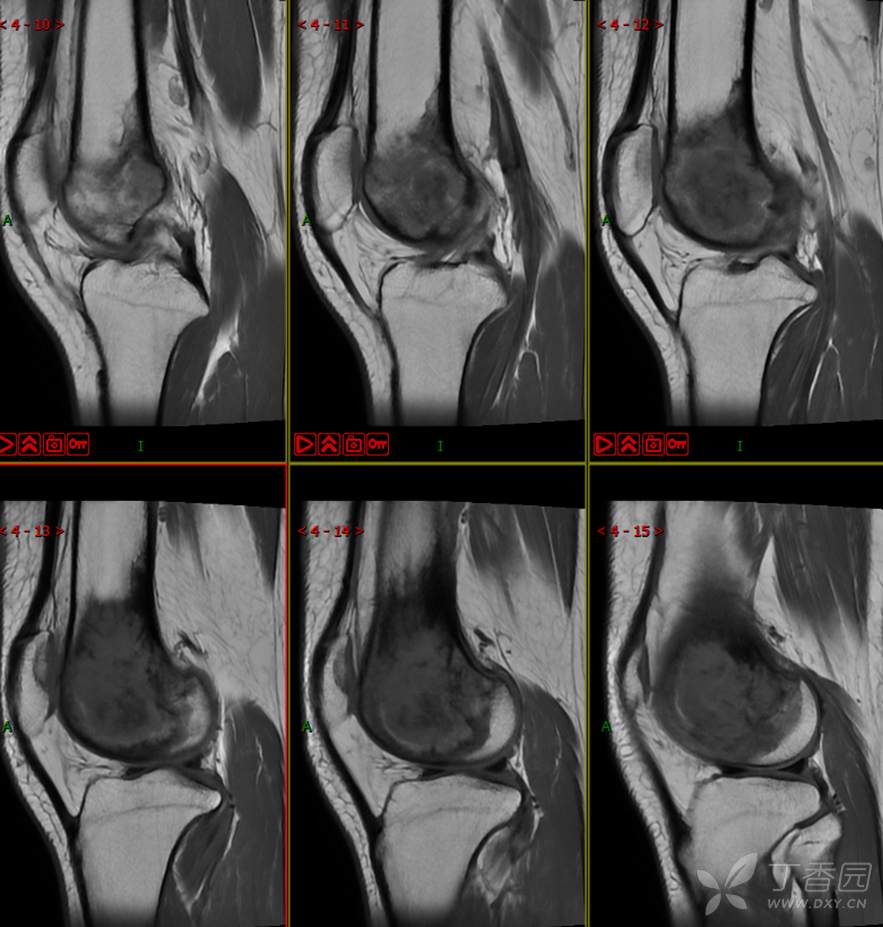

【影诊笔记497】左膝关节疼痛不适1周余就诊,有点难度~『骨巨细胞瘤』

主 诉:左膝关节疼痛不适1周余。

现病史:患者1周余前无明显原因及诱因出现左膝关节疼痛不适,活动时疼痛加重,休息后好转,无明显关节不稳及交锁,无发热、盗汗、乏力,无胸闷、憋气,无头痛、头晕,无四肢小关节晨僵。曾于外院就诊行左膝DR检查示:左股骨远端肿物。现患者为进一步治疗于我院就诊,门诊经检查后以“左股骨远端肿物”收入我科。患者自起病以来,神志清,精神可,饮食睡眠可,大小便正常,体重无明显减轻。